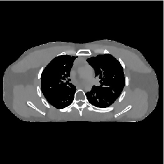

This section compares the reconstruction quality and runtime among the proposed MBIR method, PWLS-ST-, and other three MBIR methods, PWLS-EP, PWLS-DL, and PWLS-ST-. Table I shows that, for both 2D and 3D sparse-view CT reconstructions of the XCAT phantom, the proposed PWLS-ST- model outperforms PWLS-EP and PWLS-ST- in terms of RMSE. In addition, PWLS-ST- using a square transform (of size ) achieves lower RMSE than PWLS-DL using an overcomplete dictionary (of size ) for 2D sparse-view reconstructions. Fig. 3(a) and Fig. 4 show the reconstructed images for 2D and 3D phantom experiments, with different reconstruction models and different number of views. (See the corresponding error maps in the supplement.) The proposed PWLS-ST- consistently gives more accurate image reconstructions compared to other MBIR methods. Specifically, PWLS-ST- has smaller errors in the heart region (see zoom-ins in Fig. 3(a)) of 2D reconstructions than PWLS-DL and PWLS-ST-. In addition, compared to PWLS-ST-, PWLS-DL and PWLS-ST- have some ringing artifacts around the edges with high transition, e.g., edges between air and soft tissues. (See a comparison of profiles of PWLS-ST- and PWLS-ST- in the supplement.) In particular, PWLS-ST- and PWLS-DL give more visible ringing artifacts for 2D reconstruction from fewer views, and PWLS-ST- has these ringing artifacts for 3D reconstructions regardless of the number of views (see zoom-ins in Fig. 4). Table II reports runtimes of different MBIR methods in reconstructing the -views XCAT phantom scan. (FBPConvNet is a non-MBIR method and its runtime for processing a image is approximately one second with a TITAN Xp GPU.) While providing better reconstruction quality, the proposed Algorithm 1 of PWLS-ST- has shorter runtime compared to the algorithms of PWLS-DL and PWLS-ST- in Section III-A. Similar to the PWLS-EP algorithm, the reconstruction time of the PWLS-DL, PWLS-ST-, and PWLS-ST- algorithms can be further reduced by using ordered subsets [51].

| (b) 3D axial cone-beam CT experiments |

This section compares the generalization capabilities between the proposed MBIR method, PWLS-ST-, and a denoising deep NN, FBPConvNet [14], that are trained from the phantom data; in particular, we tested the trained PWLS-ST- and FBPConvNet models to phantom and clinical scan data. The results in Fig. 6 show that the non-MBIR FBPConvNet method has higher overfitting risks, compared to the proposed PWLS-ST- MBIR method. When tested on clinical scan data, PWLS-ST- achieves much more accurate reconstruction, compared to FBPConvNet. See Fig. 6(b). When tested on phantom data, FBPConvNet generates more unnatural features as the number of views reduces, although it gives lower RMSE values compared to PWLS-ST-. See zoom-ins in Fig. 6(a). The FBPConvNet results above correspond to those in the recent work [16] that FBPConvNet [14] generated some unexpected structures.